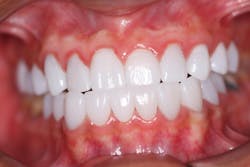

No. 2. Maxillary arch

- Extraction of nonrestorable tooth no. 3

- Endodontics, post, and core buildup with Rebilda DC (Voco)

- Selective etching, bonding with Futurabond DC, restoration with GrandioSO

- Provisional crowns fabricated using Structure 2 (Voco; figure 2)